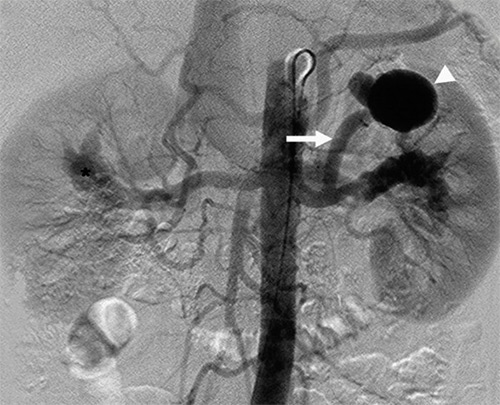

La angiografía cerebral es el estudio radiológico de las arterias y venas del cerebro. Para realizarlo se efectúa una punción en una arteria de la ingle, bajo anestesia local, para introducir un catéter (pequeño tubo), que se avanza en el interior de los vasos sanguíneos hasta el cuello. Luego, se inyecta líquido de contraste que hace posible la visualización de los vasos sanguíneos utilizando una máquina especial de rayos x denominada angiógrafo.

La angiografía cerebral sigue siendo el método más preciso para el estudio de enfermedades vasculares del cerebro, en particular de aneurismas cerebrales y malformaciones vasculares arteriovenosas.

En el caso de aneurismas, permite determinar con precisión su localización, tamaño y características morfológicas, además de entregar información hemodinámica, todos elementos fundamentales al momento de seleccionar la mejor opción terapéutica para cada paciente. La angiografía es realizada por un neuroradiólogo intervencionista con entrenamiento y experiencia adecuada, siendo asistido por un equipo de enfermeras, técnicos y auxiliares especializados.